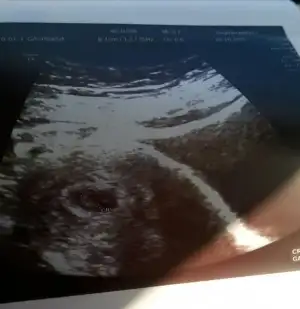

Hazirandaki gebeliğim sonlandı maalesef.pıhtılaşma olmuş ve bebeğimin kalbi durmuş.şimdi allahın izniyle tekrar hamileyim kan suşandırıcı iğne kullanıyyorum.yorum yaparmısınız usg lere.2 side karından .ilk resim 7 hafta 2.si 6+3.

Allah bağışlasın canım.evet karından,bir kızım var 7 yaşında buda 2. Miz :) kızıma kızkardeş mi erkek kardeş mi gelecek bakalım.12.haftada gideceğim tekrar belkş Dr bi tahmin yapar